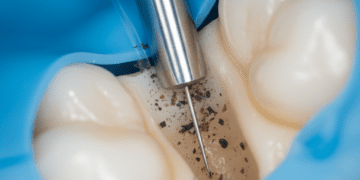

Terapia periodontal

Se a recessão estiver associada à doença periodontal, a primeira etapa é o controle da infecção, com limpeza profunda para remoção da placa bacteriana e do cálculo dental, chamada de raspagem e alisamento radicular.